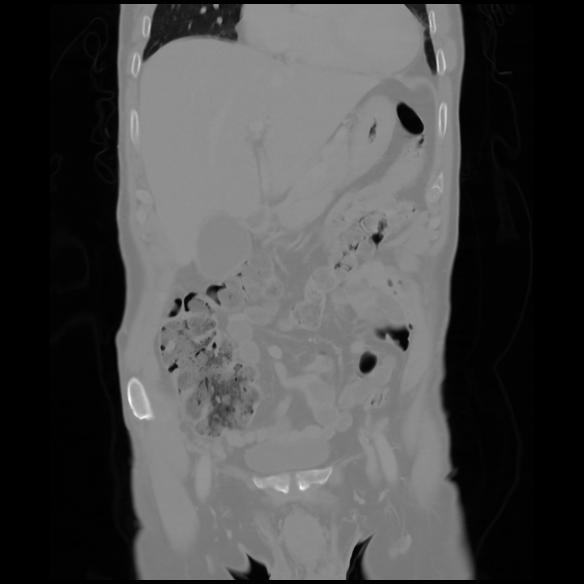

6 CUERPO,CE,Coronal,3.000,CUERPO,Coronal,